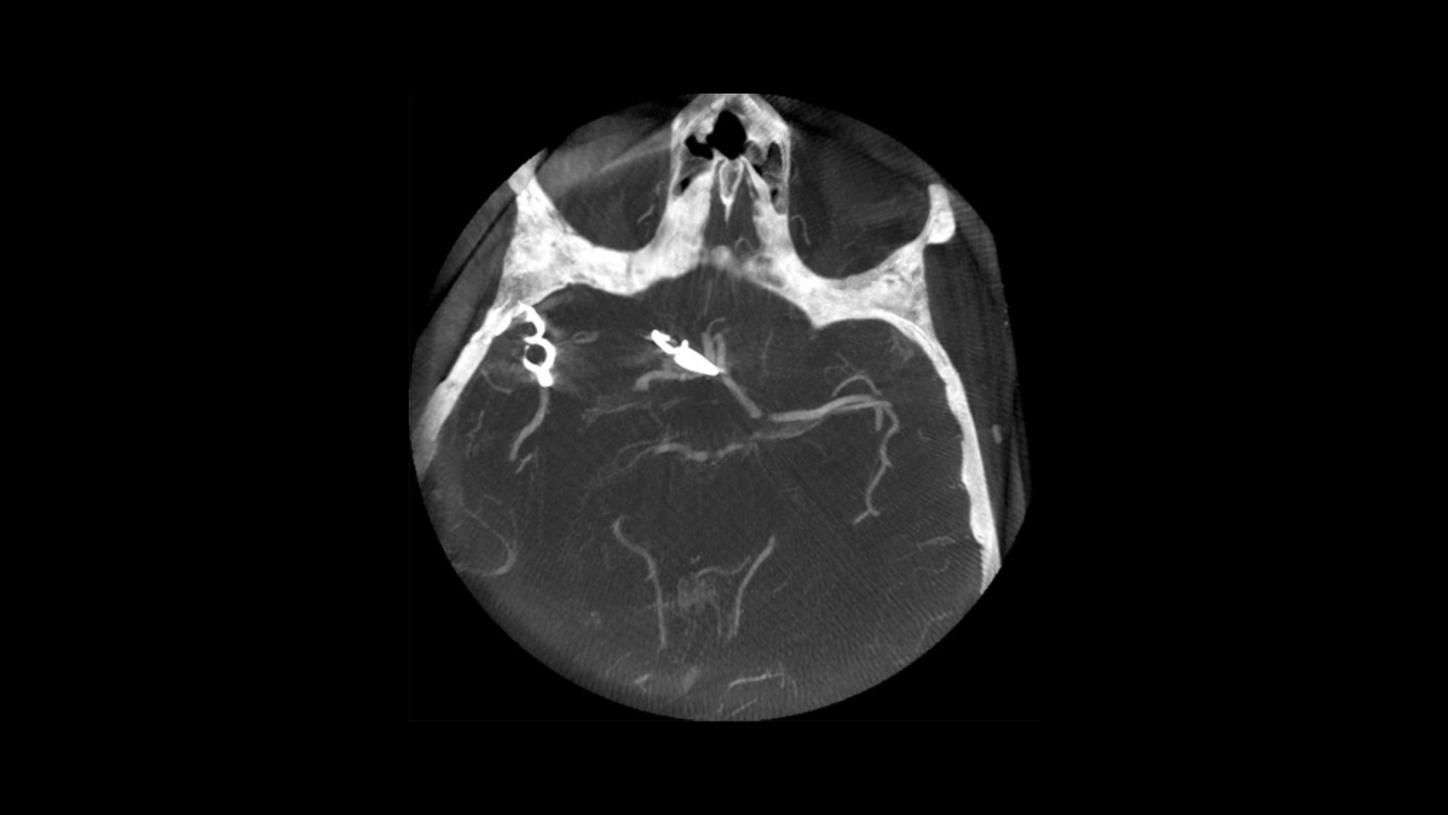

- Follow-up syngo DynaCT after clipping, with intravenous contrast media injection

- Axial maximum intensity projection of the clipped aneurysm

- Follow-up syngo DynaCT after clipping, with intravenous contrast media injection

- Axial maximum intensity projection of the clipped aneurysm